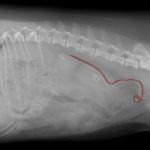

かかりつけ医で定期的に超音波検査で腎結石のモニターをしていたところ、急に腎盂が拡張してきたので早急に対応して欲しいと連絡がありました。尿管結石により尿路閉塞が起こっていました。マイクロサージェリーで尿管を2箇所切開し、尿管結石を摘除しました。術後の狭窄予防に一時的に尿管ステントを留置しています。術後翌日から、腎盂拡張は解消しましたが、術後の経過により、生体にとって異物となる尿管ステントは抜去する予定です。